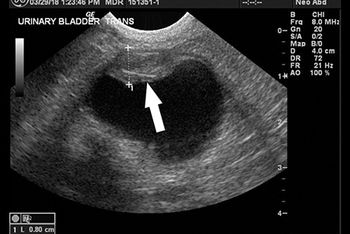

An intervention to remove urinary stones didn't alleviate this bichon frises's stranguria. See if you can spot the cause in this ultrasonogram.